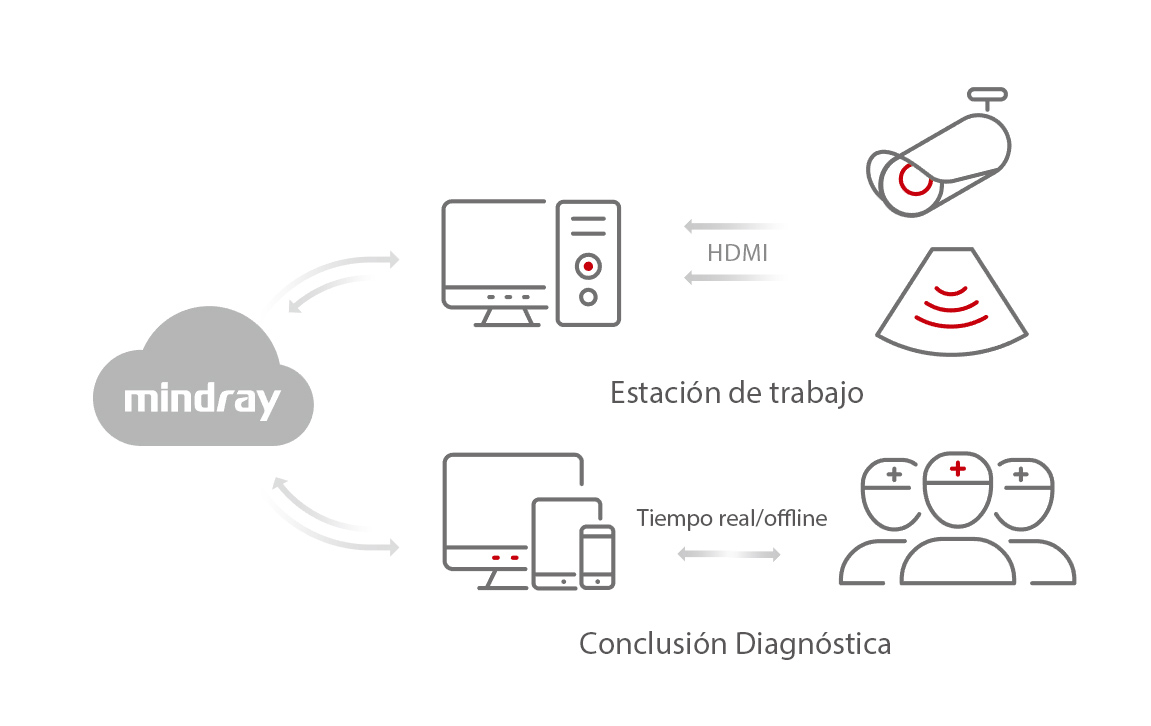

- 2. Consulta remota, capacitaciĂłn y ense?anza